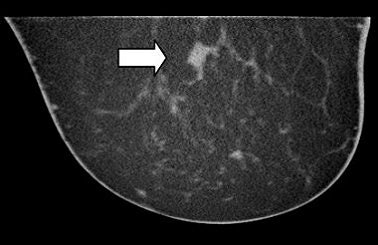

| A 7-mm cluster of suspicious microcalcifications. Coronal and axial breast CT scans show microcalcifications in an ill-defined mass (DCIS). Image courtesy of John Boone, Ph.D. |